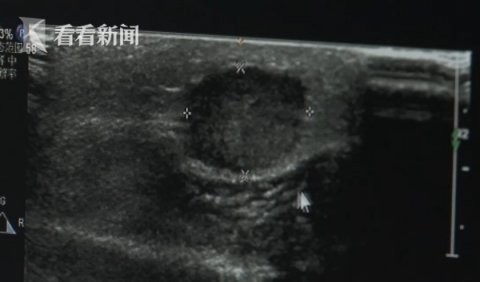

当时B超检查见到,李先生右胸乳晕位置的肿物宽度有两厘米左右,初步怀疑是良性的肿瘤。但做完病理组织检查以后就发现,李先生竟然是患上了乳腺癌,而一般男性患乳腺癌的概率很小。